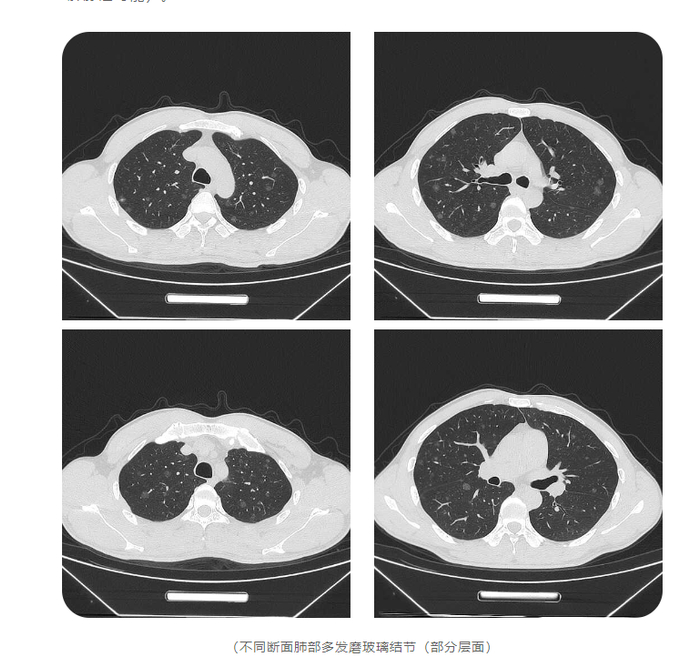

37岁的胡军(化名)最近做了个胸部CT,检查结果显示,其双肺长了557个磨玻璃结节,最大的直径1.2厘米。

“我从医快20年了,甄别过许多肺结节,这次遇到的病例非常特殊。”医生说,这些结节均大于3毫米,随机分布,密密麻麻。

胡军告诉医生,他3年前就查出多发性肺部结节,这几天出现咳痰、胸闷等症状。肺结节人工智能软件提示,其双肺竟有557个磨玻璃结节,其中高危的有26个。